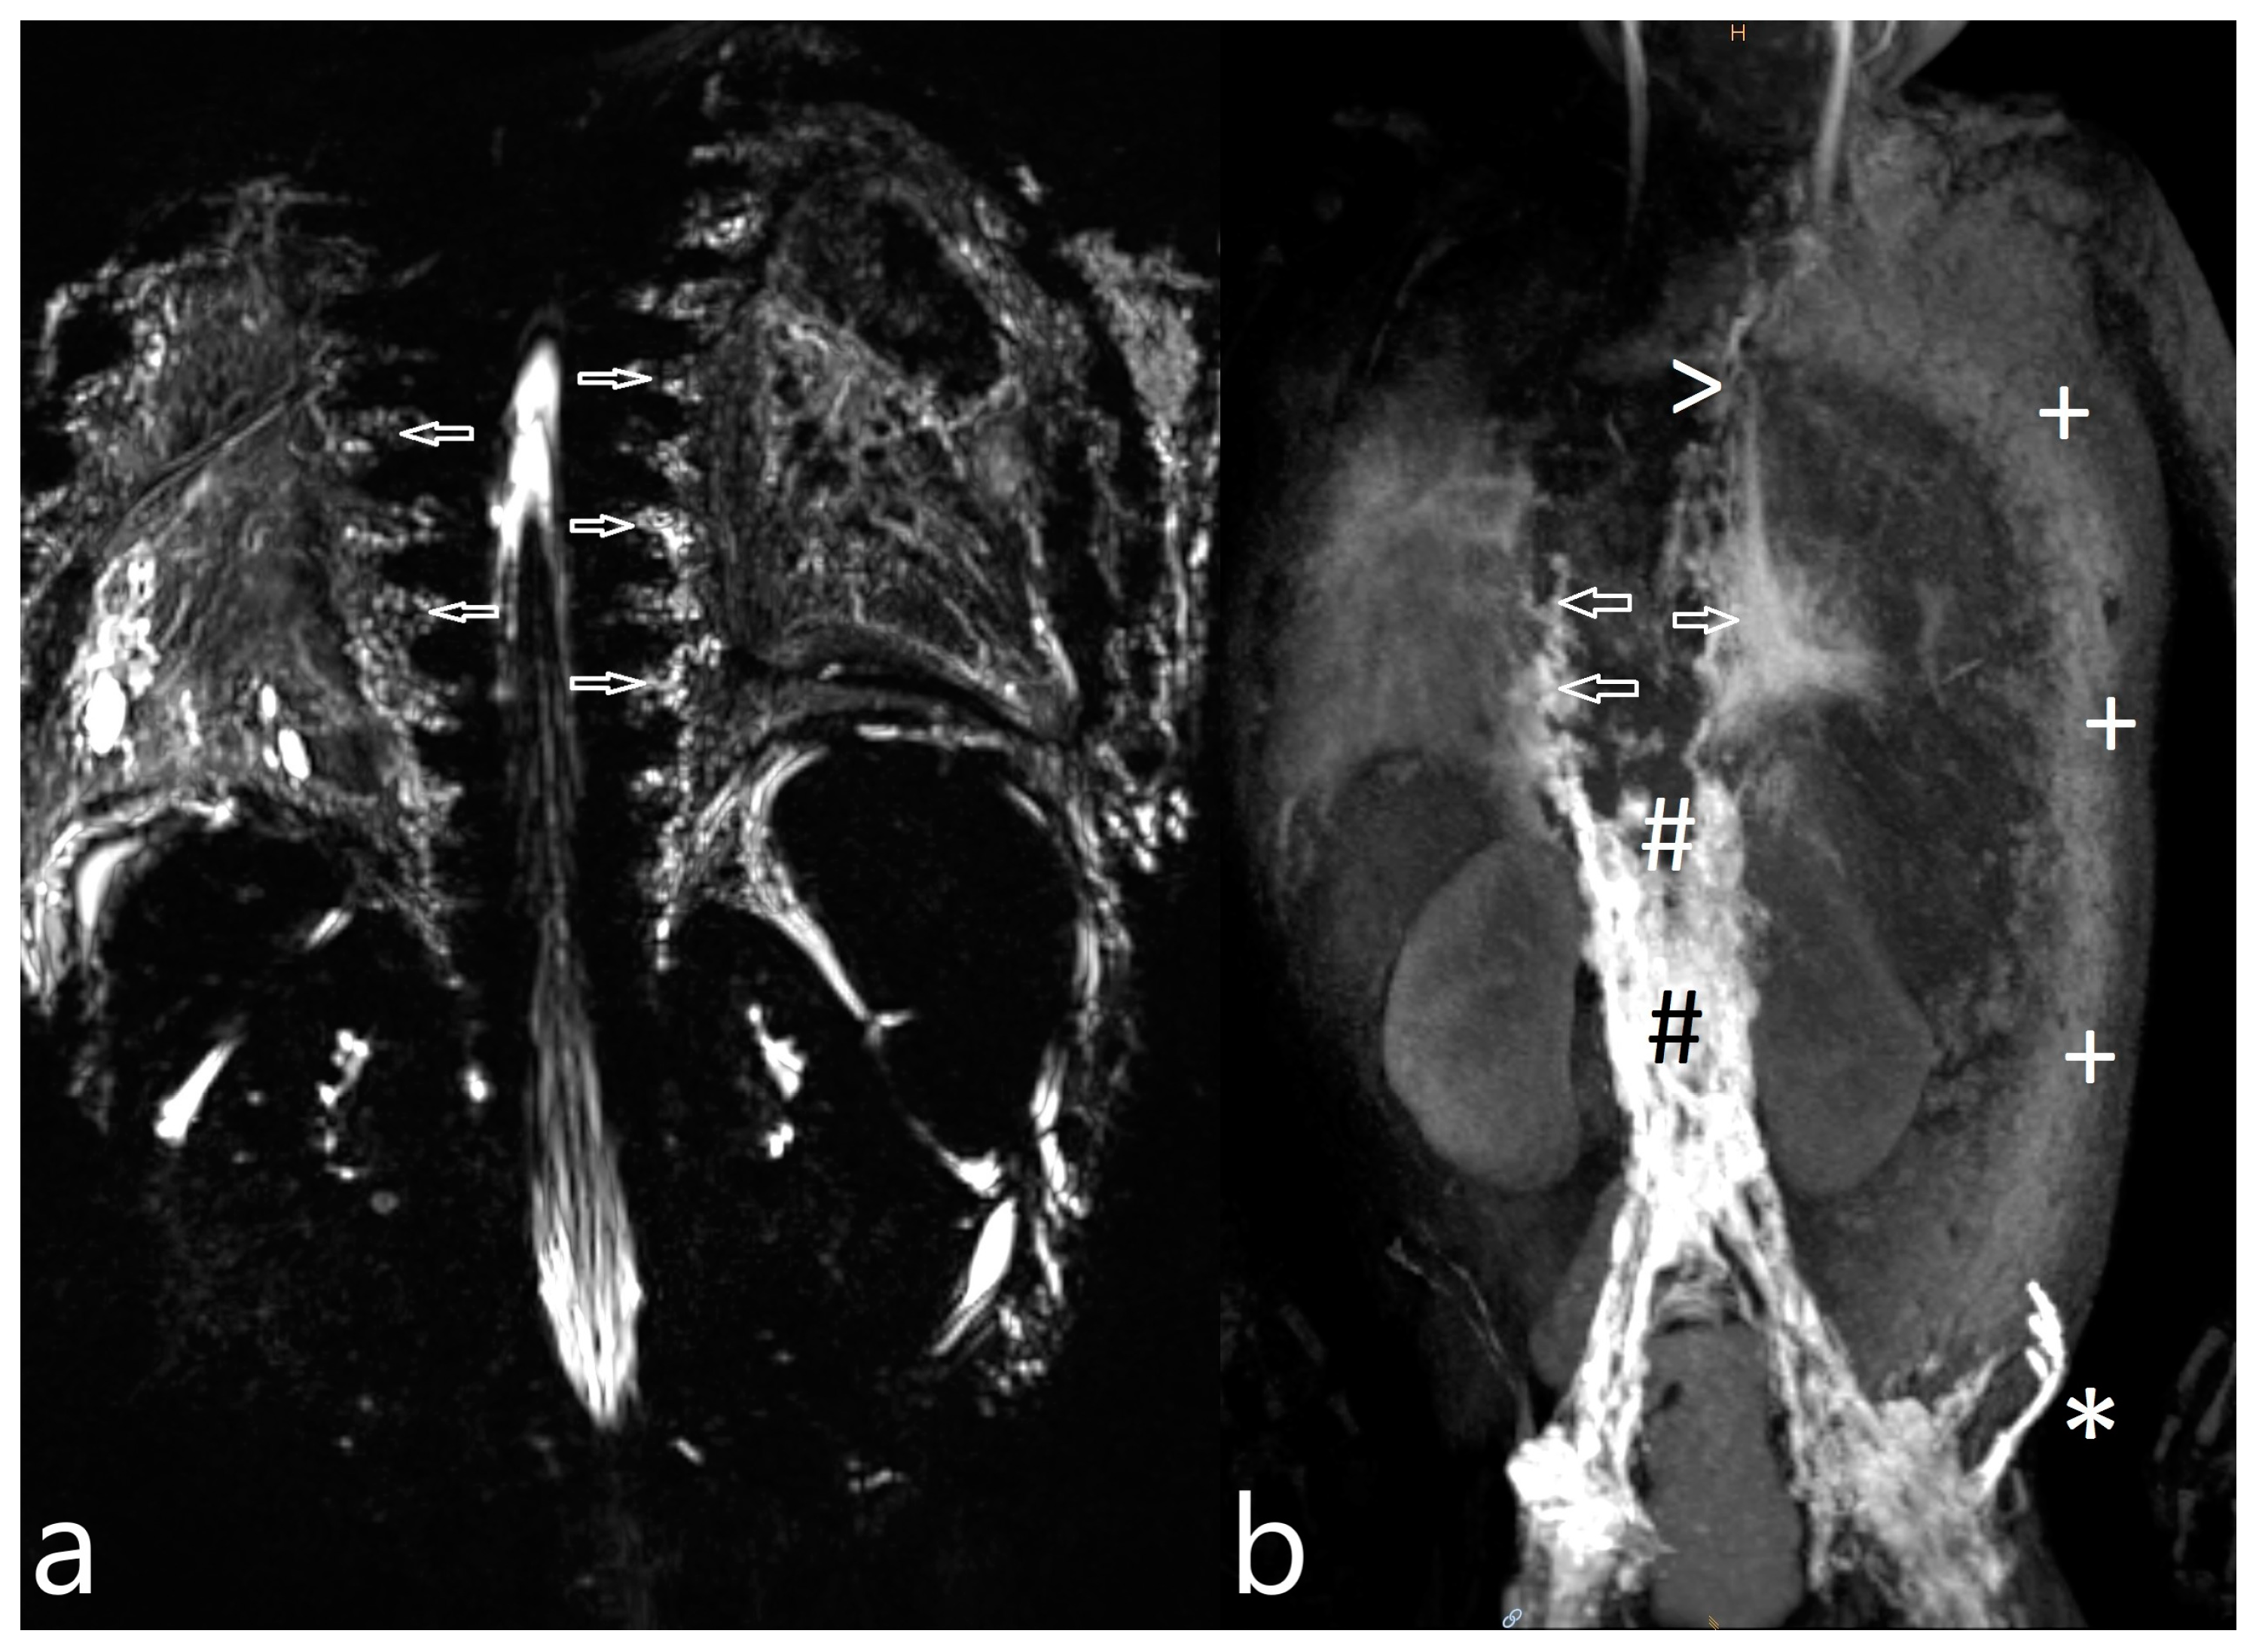

Figure 1.

Intercostal lymphatic flow (a, arrows point at it) and dermal backflow (b, * shows dermal backflow, # is the dilated lymphatic network, arrows point to a doubled thoracic duct with pulmonary effusions, + shows dermal effusions).

Noonan Syndrome: The details of our MR lymphography and dynamic contrast MR lymphangiography findings as well as the preprocedural management and outcome of the three patients with genetically confirmed Noonan syndrome are listed in Table 5. Figure 1a,b represent the typical findings of the Noonan syndrome patients. All three children’s lymphatics as well as lymphatic flow were severely abnormal. Lymphatic fistulas to the lung could be visualized in two children.

For Noonan syndrome, our investigations are in line with previously published data that recently characterized lymphatic abnormalities in this cohort by retrograde intercostal flow, pulmonary lymphatic perfusion and thoracic duct abnormalities [15]. Besides the characterization of lymphatic abnormalities, the confirmation of lymphatic fistulas enabled us to conduct a selective lymphatic intervention in one patient.